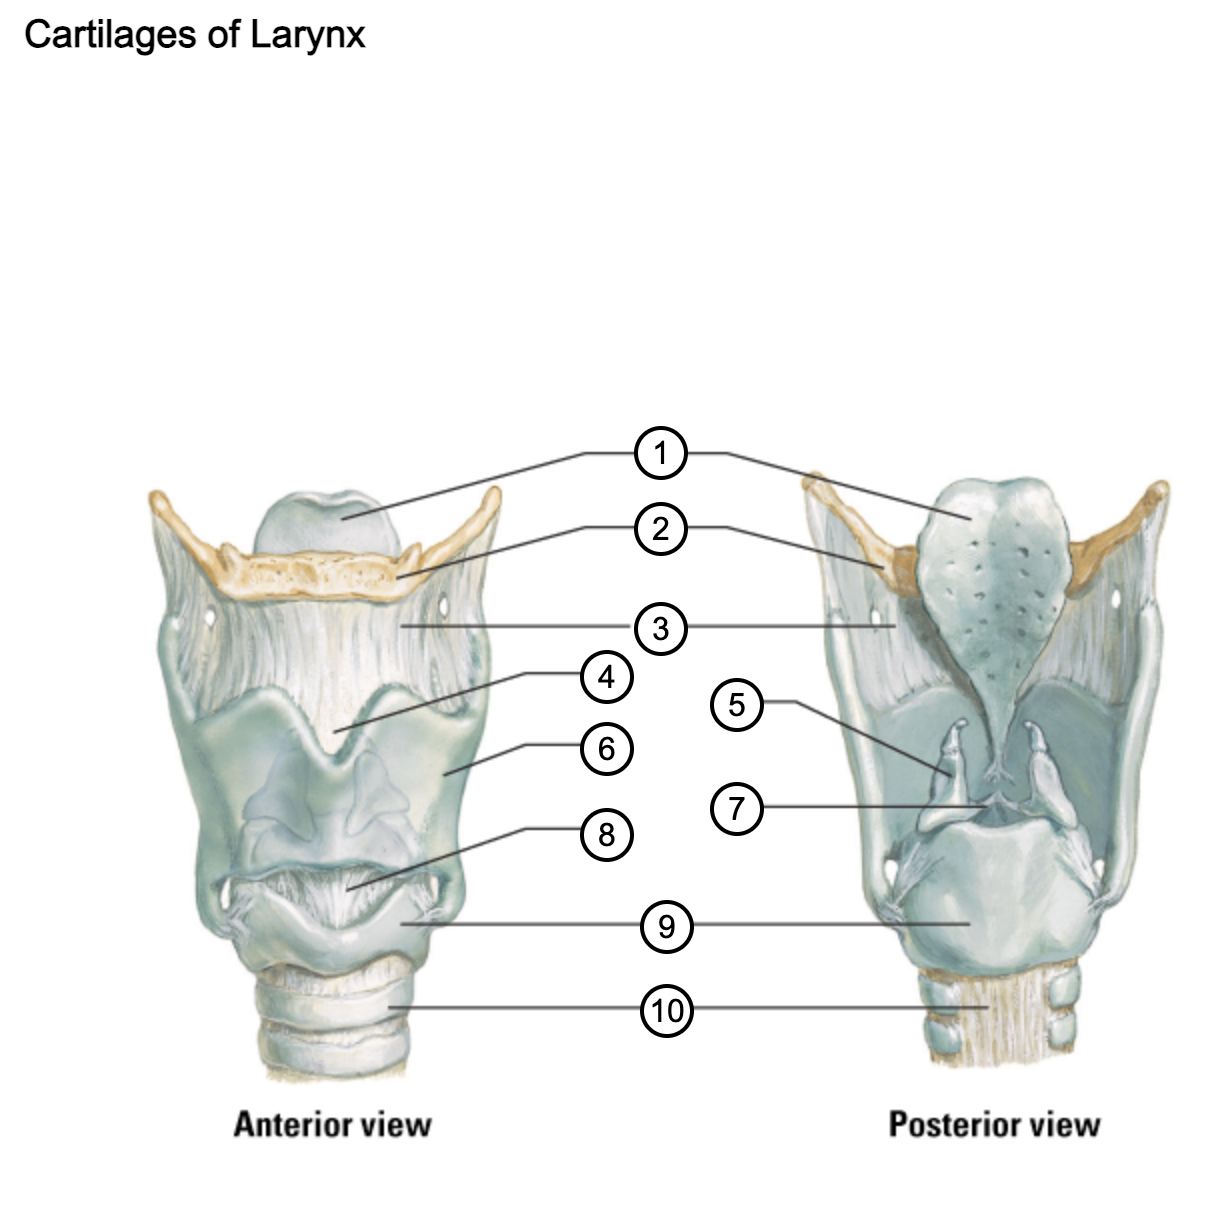

1

epiglottis

2

hyoid bone

3

thyrohyoid membrane

4

superior thyroid notch

5

arytenoid cartilage

6

lamina of thyroid cartilage

7

vocal ligament

8

median cricothyroid ligament

9

cricoid cartilage

10

trachea